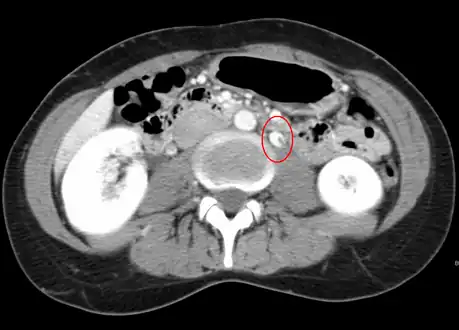

Compression of the left renal vein (marked by the arrow) between the superior mesenteric artery (above) and the aorta (below) due to nutcracker syndrome.

Thrombosis in the left renal vein associated with dilation.